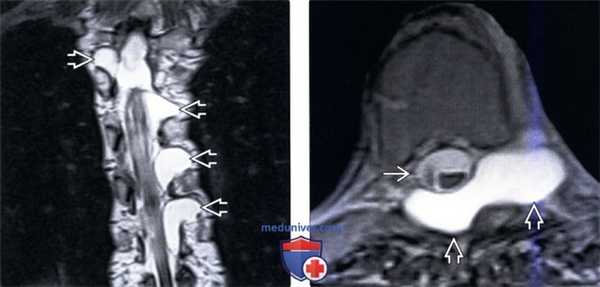

(Слева) Т2-ВИ, фронтальная проекция (синдром Марфана): двусторонние дивертикулы твердой мозговой оболочки (латеральные менингоцеле), распространяющиеся в межпозвонковые отверстия и оттесняющие спинной мозг.

(Справа) Т2-ВИ, аксиальная проекция (синдром Марфана): смещение дурального мешка крупным латеральным менингоцеле, продолжающимся в дорзальный отдел спинномозгового канала. Обратите внимание на выраженное ремоделирование костных стенок канала с увеличением размеров канала и нивелированием объемного воздействия кисты на спинной мозг.